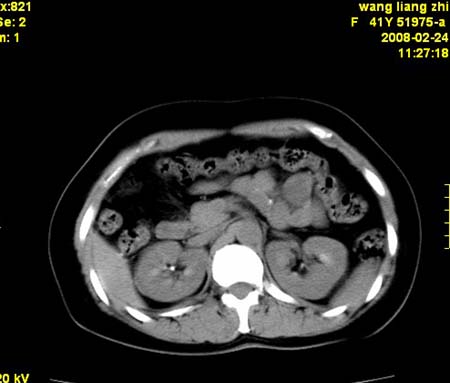

以下是引用dyqct在2009-8-23 16:17:00的发言:[br]考虑:1、造影剂进入腹腔、结肠旁沟、肝周;[br] 2、子宫明显增大(腺肌增生症?);[br] 3、膀胱显影是由于造影剂吸收后经肾分泌进入膀胱的;[br] 4、建议mri检查子宫。